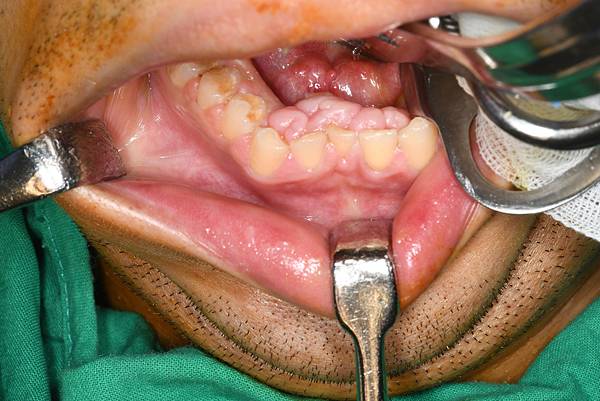

有個33歲男性患者,是被家人推來門診的,是固定在輪椅上,不固定著會滑下輪椅的狀態,感覺得到他來看門診家人也頗辛苦,他四肢形體部分萎縮,意識指令無法obey,但肌張力還算強,現在有氣切和鼻胃管。這次是媽媽和外籍看護陪同來看診。媽媽主訴患者牙齦增生,是居家口腔照護的牙醫師定期到宅洗牙時多次建議要來醫院切除,於是他們前來看診。 媽目測大概50多歲左右(?),我覺得她精神和身體維持保養得不錯,我想我小孩30歲時我應該無法這麼好。口內看其實在腭側和舌側都明顯有牙齦增生,尤其在前牙區,內側的牙冠表面都被蓋住了,媽媽說其實這樣他們這樣幫患者口腔清潔很難清,所以決定帶他來處理。

雖然幾乎整個口腔都有牙齦增生,我們和媽媽建議先處理上下前牙就好,之後久了可能也還會再增生。而且全身麻醉術後通常也需要患者能深呼吸幫助肺部擴張,我們無法知道他術後是否自呼的很好,所以出院時間很難確定,不過通常術後隔天可以出。媽媽了解了!